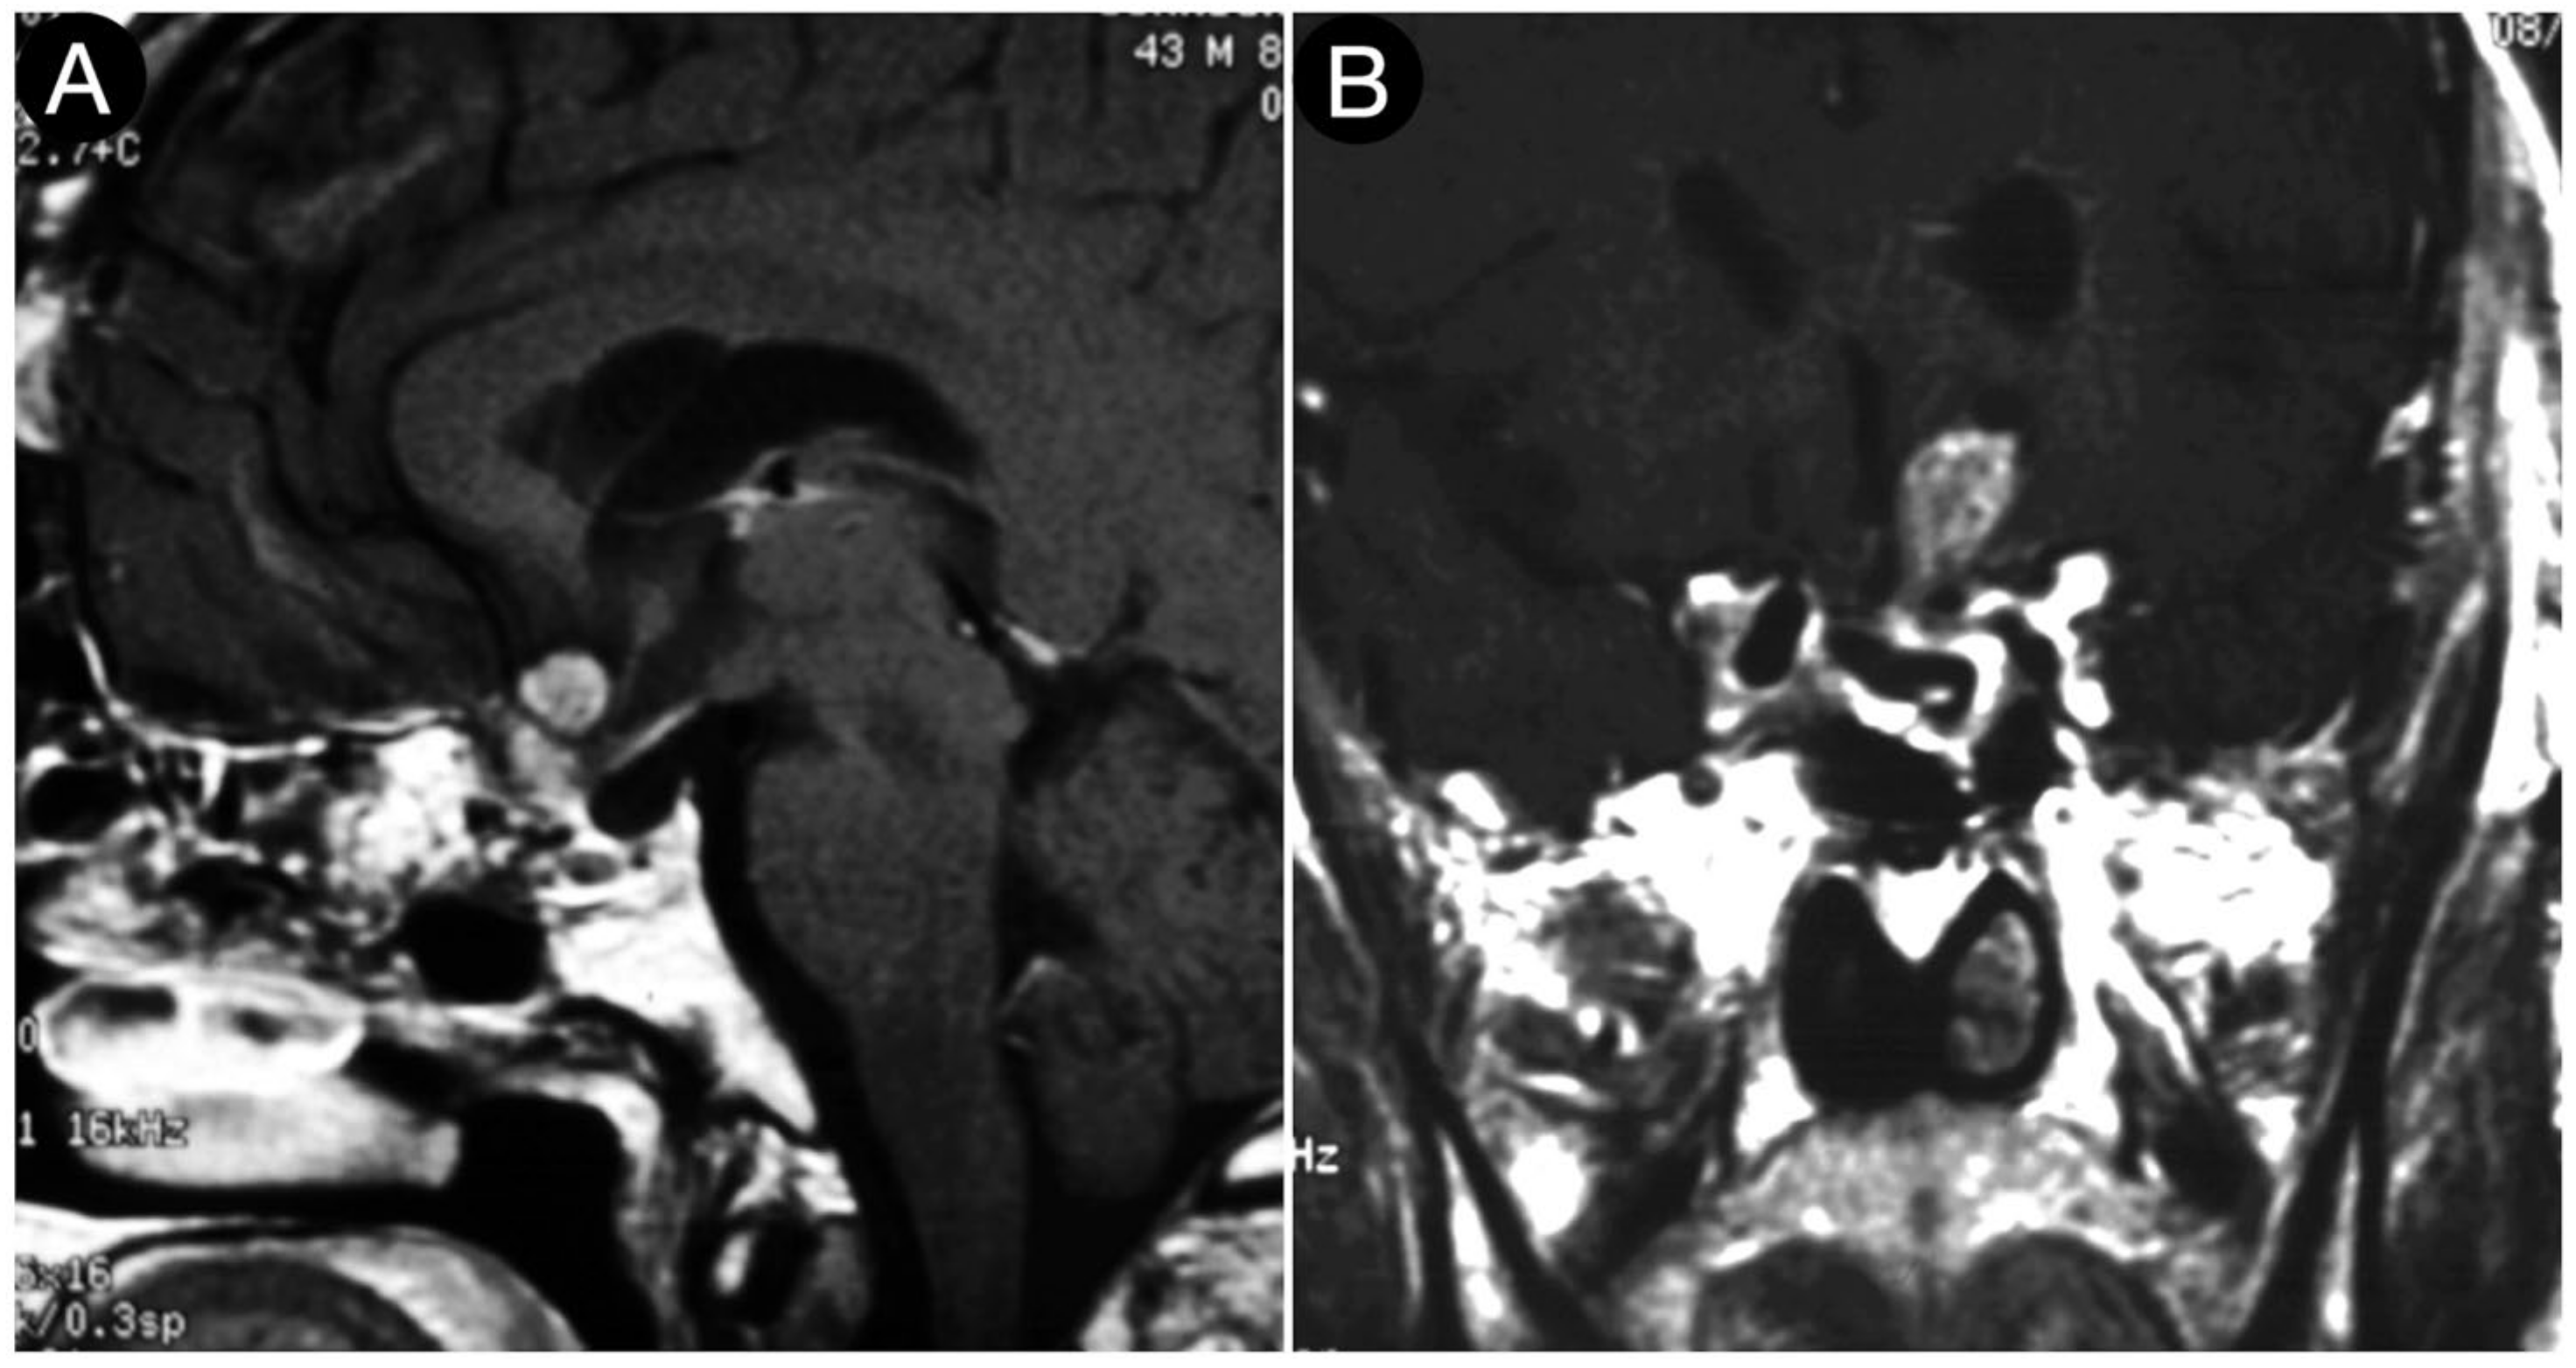

Case #8: Aggressive ACTH Tumor with Multiple Recurrences

3.7. Coexisting Cerebral Aneurysms

3.8. Residual and Recurrent Tumors